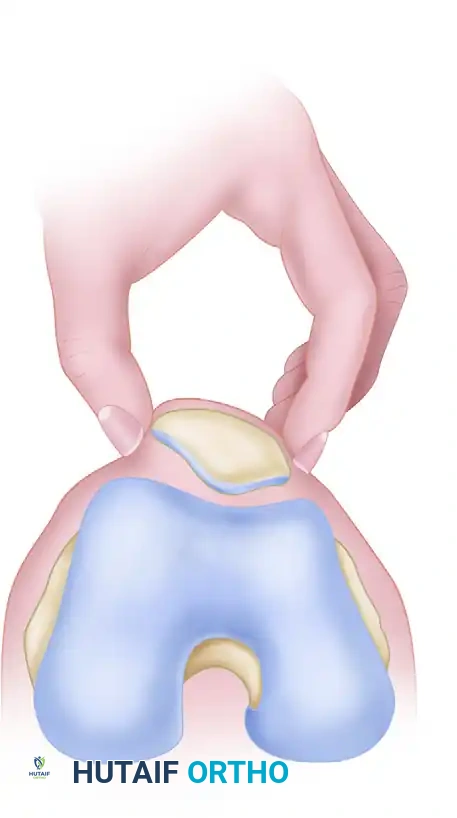

1. Passive Patellar Tilt Test

This test evaluates the tightness of the lateral retinaculum.

- Technique: The patient lies supine with the knee fully extended and the quadriceps relaxed. The examiner attempts to lift the lateral edge of the patella away from the lateral femoral condyle.

- Interpretation: The patella should remain seated in the trochlea. An excessively tight lateral restraint is diagnosed when the patella cannot be lifted past the horizontal plane, demonstrating a neutral or negative angle.

2. Patellar Glide Test

This test assesses the integrity and tension of both the medial and lateral restraints.

- Technique: The knee is flexed to 20 to 30 degrees (often supported by a small pillow) to engage the patella in the trochlear groove. The quadriceps must be completely relaxed. The patella is conceptually divided into four longitudinal quadrants. The examiner applies medial and lateral displacing forces.

- Interpretation:

- A lateral glide of ≥ 3 quadrants indicates an incompetent medial restraint (e.g., torn MPFL).

- A medial glide of ≤ 1 quadrant indicates a pathologically tight lateral retinaculum.

- A medial glide of ≥ 3 quadrants suggests a globally hypermobile patella.

- Ideal candidate for lateral release: Medial and lateral glide of 2 quadrants or less, combined with a negative tilt test.